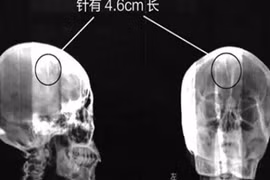

Kỳ lạ kim khâu nằm trong đầu mà không hay biết

Gần nửa đời người, người phụ nữ khốn khổ mới tìm ra nguyên nhân cơn đau đầu hành hạ từ năm 2 tuổi là do kim khâu nằm trong đầu.